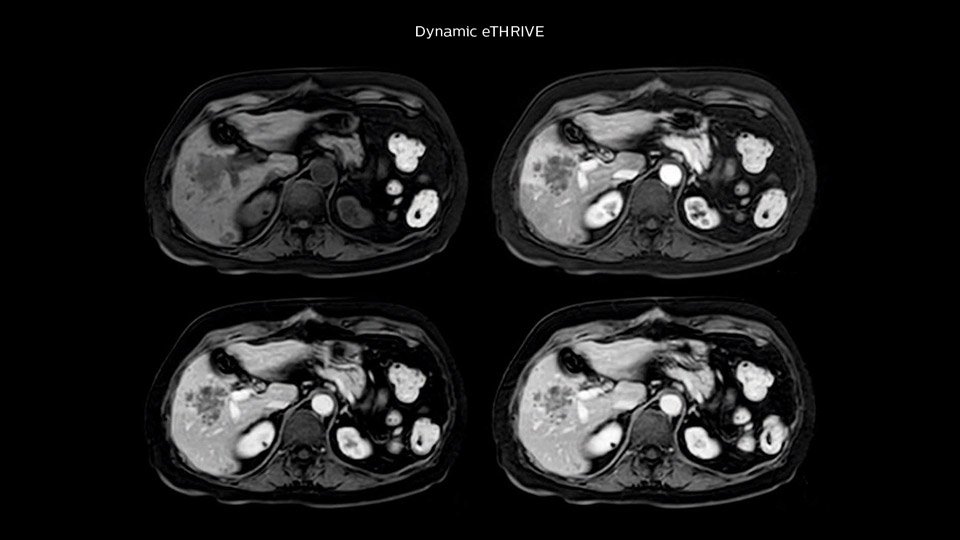

In this example the image quality of the MultiVane XD images is evidently better than in the images without MultiVane XD. Ingenia 1.5T with dS Torso coil solution.

“Our liver exams are quite fast,” says Dr. Baumann. “If the patient tolerates it, we use an arms-up position to reduce the FOV and speed up the exam with dS SENSE.” “We acquire one transversal high resolution T2-weighted sequence with 3 mm slice thickness, for example for pancreas or liver lesions. Then we also add a T2 fat suppressed MultiVane XD SPIR sequence. We perform these two routinely in our liver imaging. We use high dS SENSE factors to significantly shorten scan times to 2-4 minutes, which can improve our protocol; it’s a very robust scan.” “We include mDIXON for the dynamic sequences because of the robust and homogeneous fat suppression we get with that. We had been using eTHRIVE, but we are now quite happy with mDIXON. Sometimes we use a medication to calm the bowels, to further improve the image quality.”